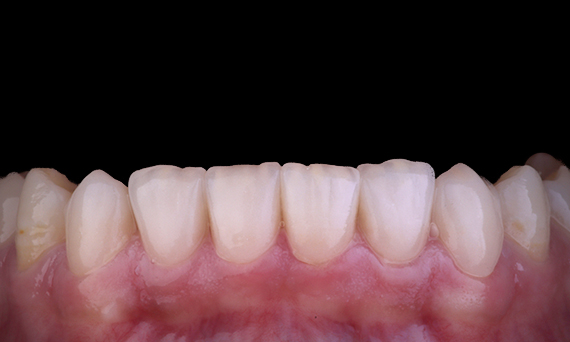

Le patient s’est présenté avec une pulpite irréversible sur la dent 46. Sur la radiographie préopératoire, la dent 46 présente une racine distale supplémentaire (morphologie de la dent Radix Entromolaris). Un balayage CBCT a confirmé la présence d’une racine DL avec une courbure radiculaire sévère. Une sélection minutieuse des limes est essentielle pour cette racine DB délicate.

Dr Jack Lin, Endodontiste, Sydney, NSW Australie